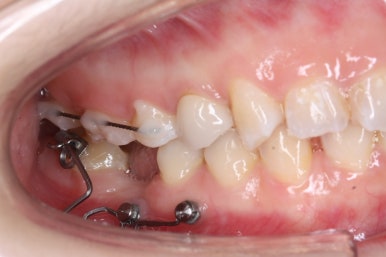

치료 과정을 순차적으로 보겠습니다.

임플란트를 식립하기 위한 공간이 서서히 확보가 되어 가는 것이 보입니다. 어금니만한 사이즈로 공간이 확보가 되면 식립이 이뤄지죠.

불과 4개월만에 장리가 충분히 확보된 모습입니다.

키다리아저씨치과에서는 부산부분교정을 통해 어금니가 충분히 뒤로 이동을 하면서 공간이 확보 되었다고 생각되면 임플란트 식립이 완료가 될 때까지 유지를 해줍니다. 유지가 원활히 되지 않으면 임플란트가 최종 완성되는 몇 개월간 다시 쓰러질 수 있거나 위치가 변할 수 있기 때문이죠.

화살표를 보시면 교정치료를 하지 않은 윗니들을 변화가 생길 것을 미리 염려해 철사를 붙여두었습니다. 임플란트 식립이 필요로 한 옆 치아에도 붙이고 미니스크류를 연결을 시켜 놓는 등 적극적으로 힘을 주는 과정이 아닌 현재를 유지하기 위한 장치입니다.